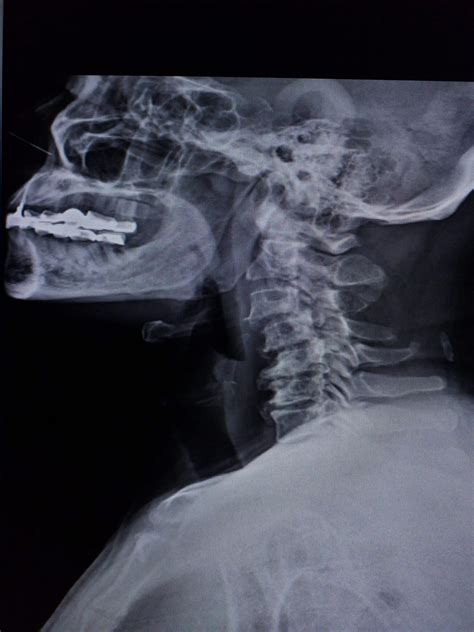

Understanding the complexities of spinal health is crucial for maintaining overall well-being, especially when it comes to conditions that affect the cervical spine. One such condition is Grade 1 Retrolisthesis, a term that might not be familiar to many but is significant for those experiencing spinal issues. This condition involves the posterior displacement of one vertebra relative to the adjacent vertebra, typically by less than 25% of the vertebral body's width. This blog post delves into the intricacies of Grade 1 Retrolisthesis, its causes, symptoms, diagnosis, and treatment options.

Diagnosing Grade 1 Retrolisthesis

Diagnosing Grade 1 Retrolisthesis typically involves a combination of physical examinations and imaging tests. The diagnostic process may include:

• Imaging Tests: X-rays, CT scans, and MRI scans to visualize the spine and identify any misalignments.

Imaging tests are particularly crucial for diagnosing Grade 1 Retrolisthesis, as they provide a clear view of the vertebrae and any slippage. MRI scans are often preferred for their detailed images of soft tissues, which can help identify nerve compression and other issues.